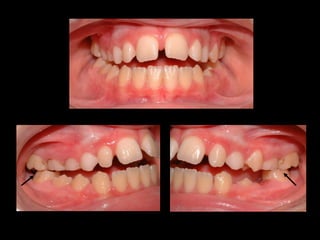

BARRA PALATINA CORRIGIENDO LA ROTACIÓN MOLAR SE PUEDE GANAR 1-2 MM DE LONGITUD DE ARCADA POR LADO

BARRA PALATINA CORRIGIENDOLA ROTACIÓN MOLAR SE PUEDE GANAR 1-2 MM DE LONGITUD DE ARCADA POR LADO